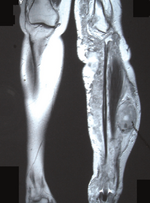

Для данного заболевания характерно появление большого количества нейрофибром, как кожных, так и плексиформных. Кожные нейрофибромы представлены небольшими доброкачественными и ограниченными новообразованиями. Они располагаются подкожно, растут на оболочках мелких нервов кожи. Плексиформные нейрофибромы развиваются на крупных нервах и приводят к нарушению их функций[26]. Также плексиформные нейрофибромы характеризуются своими большими размерами. Встречаются у 30 % больных нейрофиброматозом I типа[22].

Клинически повреждение нерва проявляется хроническими болями, онемением и/или параличами мышц.